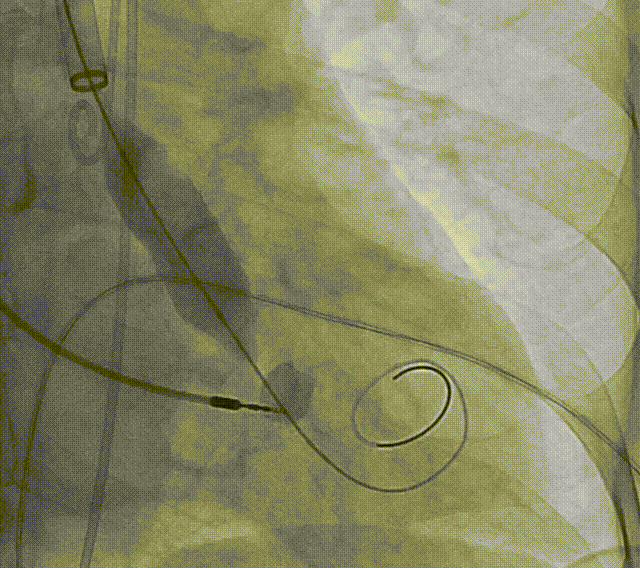

患者病史 术前超声提示:主动脉瓣退行性病变;中-重度狭窄并轻度返流;中-重度三尖瓣返流;中度肺高压 术前CT 三叶瓣,瓣叶增厚轻度钙化,右无交界有粘连,预计可以扩开,主动脉根部直径23.7mm,LVOT直径24.3mm,呈直筒型;双侧冠脉开口高度可,瓣叶长度小于冠脉开口上缘到主动脉根部的距离;窦部空间可,STJ、升主动脉内径可;主动脉水平夹角43.6°,非横位心;主动脉弓角、弓距可,左室内径可;外周入路无明显迂曲,有零星散状钙化,双侧股动脉内径可,均能通过20F大鞘,右股低分叉。 手术策略 推荐右侧股动脉为主入路使用20F大鞘,左侧股动脉为辅入路,右股分叉上方1cm穿刺;推荐使用22mm球囊预扩,预装AV26瓣膜,备AV29瓣膜,初始定位为真实瓣环上方3mm,瓣膜释放过程中释放张力使其自然下滑,工作位观察瓣膜稳定性,最终理想位置为零位;左右重合位:RAO23°CAU32°;右窦居中位:LAO5°CAU12°;左冠切线位:LAO34°CRA14°。 手术过程 术中右股动脉痉挛,内径变为3.8mm,遂更换左腋动脉入路;18球囊预扩,后植入AV26 ProStyle A®瓣膜;瓣膜精准释放于目标位置,超声显示无明显瓣周漏,血流动力学即刻改善。 术中右股动脉痉挛,内径变为3.8mm,更换左腋动脉 主动脉根部造影 18球囊预扩 初始定位 工作位观察 术后即刻表现:无瓣周漏,术后峰值压差10mmHg 术后3天复查超声峰值压差14mmHg Prostyle A®预装干瓣——助力临床最优化解决方案: 轻松过弓,精准可控:该病例经左腋动脉入路,输送系统较细的尺寸+柔顺的输送系统通过性能得到了很好的验证; 释放稳定:平衡的径向支撑力降低了释放过程中的张力,流入端小锥角设计能够迅速锚定贴边,80%可回收使得观察位和释放后的位置差距减少,大大提高了释放过程中的精准性,能够轻松应对高难度病例; 预装干瓣 便捷顺安:金仕生物专利抗钙化技术运用纳米技术去除组织内的细胞碎片和磷脂,封闭游离醛基,从根本上阻断了瓣膜钙化的多项因素,显著提升了瓣膜的耐久性;同时,相比较传统戊二醛保存方式,干式存储最大限度的保留心包的亲水亲油平衡,还原组织天然曲柔性,进一步保障了瓣叶开合,保证长期耐久性; 谢年谨教授 广东省人民医院 谢年谨教授指出:“对于外周血管条件较差的心脏瓣膜病患者,腋动脉路径凭借其更直接的解剖通路与更稳定的输送环境,为手术安全提供了重要保障,尤其适用于股动脉入路失败的复杂病例。该路径不仅能显著降低血管损伤、出血等并发症风险,还能通过更清晰的操作视野提升手术成功率;尤其在高龄、动脉硬化严重的患者群体中,腋动脉路径的适应性优势更为突出。 专家简介 荆志成 广东省人民医院 谢年谨 广东省人民医院 刘勇 广东省人民医院 · END ·